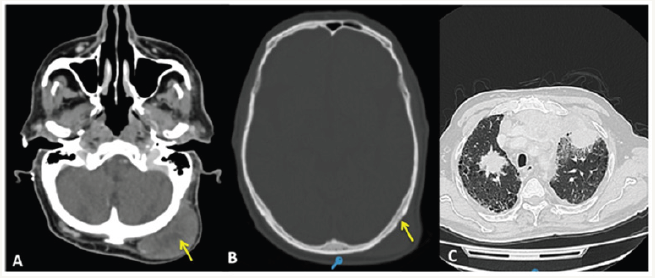

Figure 1: 1A. CT scans showing a nodular mass in the left occipital region of the scalp (yellow arrow). 1B.Low density changes in the external table of the cranium are evidenced (yellow arrow); these ariations are suggestive of metastatic disease. 1C. Pulmonary secundarism. A speculated mass is shown in the upper right lobe; bilateral nodules with irregular borders and ground-glass attenuation are also seen

We present the case of a 77-year-old male patient who was referred to the head and neck surgery service for a skin lesion on the scalp. He complained of a painless, ulcerated, elevated nodule, with 1-year progression. A full thickness resection with a 1cm margin was performed, and AFX was diagnosed after final immunohistochemistry (IHC) analysis. The AFX recurred after 2years, with an ulcerated, firm, erythematous scalp nodule associated with an enlarged neck and supraclavicular lymph nodes. A CT scan showed bone and lung secundarism as well as cervical, supraclavicular, and mediastinal adenopathies Figure 1. A fine-needle aspiration (FNA) biopsy confirmed both primary and secondary lesions Figure 2. The oncological board committee recommended surgical and adjuvant treatment; however, the patient’s condition worsened, and the family and attending team ultimately decided to submit to palliative care.